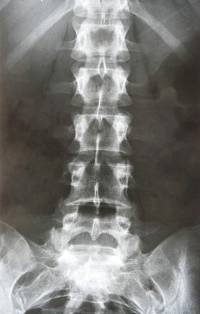

第三步:X光脊椎照片诊断

脊医会观察脊椎X光片各椎间的变化,脊柱轴线变异情况,椎体后缘联线变异情况。脊椎错位时会出现的仰位、倾位、仰旋、倾旋和侧旋等改变。各椎间关节形态或位移都属颈椎关节错位的表现。观察各椎间盘变性、椎间关节骨质增生,各韧带钙化的部位、程度等。并与第一、二步定位诊断结合分析,作出最后的诊断结果。

X光脊椎照片诊断的重要性:

1、排除脊柱肿瘤、结核、骨折、脱位及类风湿、痛风等病症。

2、分析椎间关节错位的部位及方向。

3、分析椎间盘变化程度,骨质增生部位与症状部位的关系。